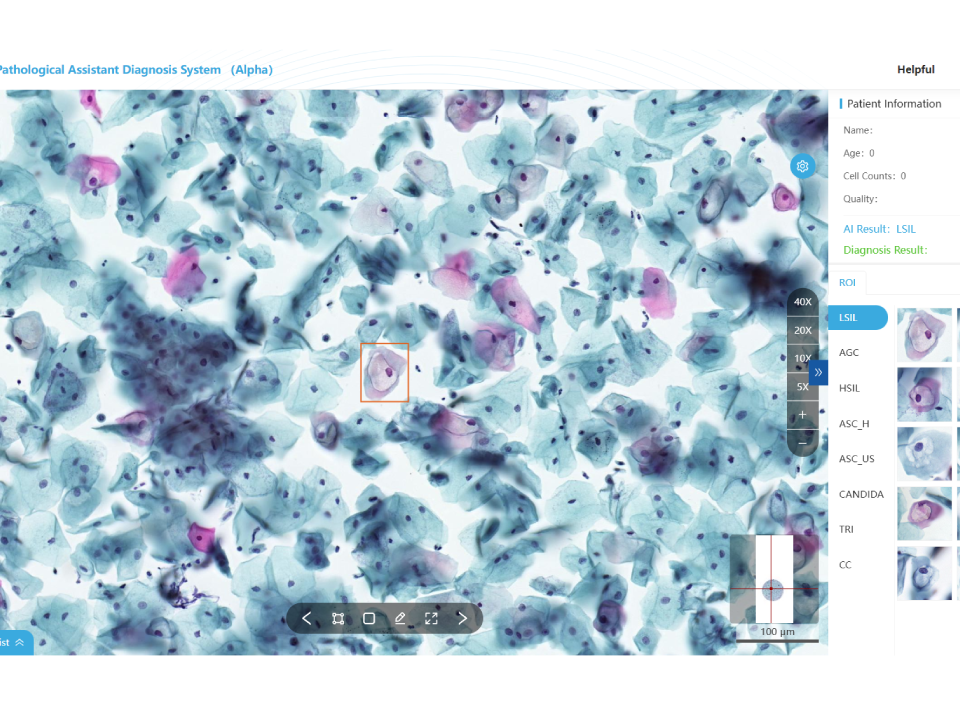

Cervical Cytology Assistant Diagnostic Module

Automatic recognition of 15 cell types. Accurate identification to reduce misdiagnosis. One-click report generation, dual-screen slide reading, interfacing with multiple systems. Validated by multi-center clinical trials: sensitivity ≥ 95%, specificity ≥ 85%. Whole slide analysis with TBS standard report. Customizable report template.

Cervical Cytology Assistant Diagnostic Module

Automatic recognition of 15 cell types. Accurate identification to reduce misdiagnosis. One-click report generation, dual-screen slide reading, interfacing with multiple systems. Validated by multi-center clinical trials: sensitivity ≥ 95%, specificity ≥ 85%. Whole slide analysis with TBS standard report. Customizable report template.

Cervical Cytology Assistant Diagnostic Module

- Automatic recognition of 15 cell types.

- Accurate identification to reduce misdiagnosis.

- One-click report generation, dual-screen slide reading, interfacing with multiple systems.

- Validated by multi-center clinical trials: sensitivity ≥ 95%, specificity ≥ 85%.

- Whole slide analysis with TBS standard report.

- Customizable report template.

Cervical Cytology Assistant Diagnostic Module

- Automatic recognition of 15 cell types.

- Accurate identification to reduce misdiagnosis.

- One-click report generation, dual-screen slide reading, interfacing with multiple systems.

- Validated by multi-center clinical trials: sensitivity ≥ 95%, specificity ≥ 85%.

- Whole slide analysis with TBS standard report.

- Customizable report template.